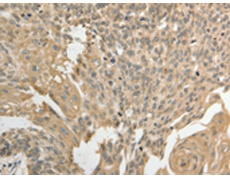

IHC positive control:

Human cervical cancer and Human ovarian cancer

IHC Recommend dilution:

50-200